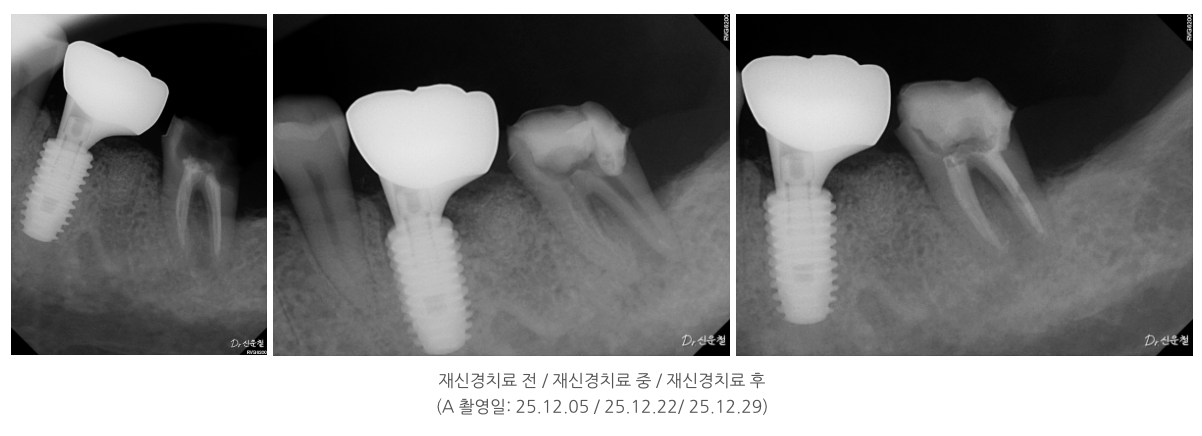

중요한 건 ‘과거 치료’가 아니라 ‘지금 상태’

이 두 경우 모두에서

치료 시작 전 가장 중요했던 기준은

과거에 어떤 치료를 받았는지가 아니라,

- 지금 이 치아 안쪽에 다시 접근할 수 있는 여지가 있는지였습니다.

치아 안쪽을 직접 확인하면서

남아 있는 길이 있는지

다시 정리가 가능한 상태인지 를 기준으로 판단했고, 그 결과

두 경우 모두 발치 대신 신경치료를 진행할 수 있었습니다.

이번 사례들 역시

치료가 쉬워서가 아니라,

치아 안쪽을 어디까지 확인했는지를 기준으로

치료 방향을 정했습니다.